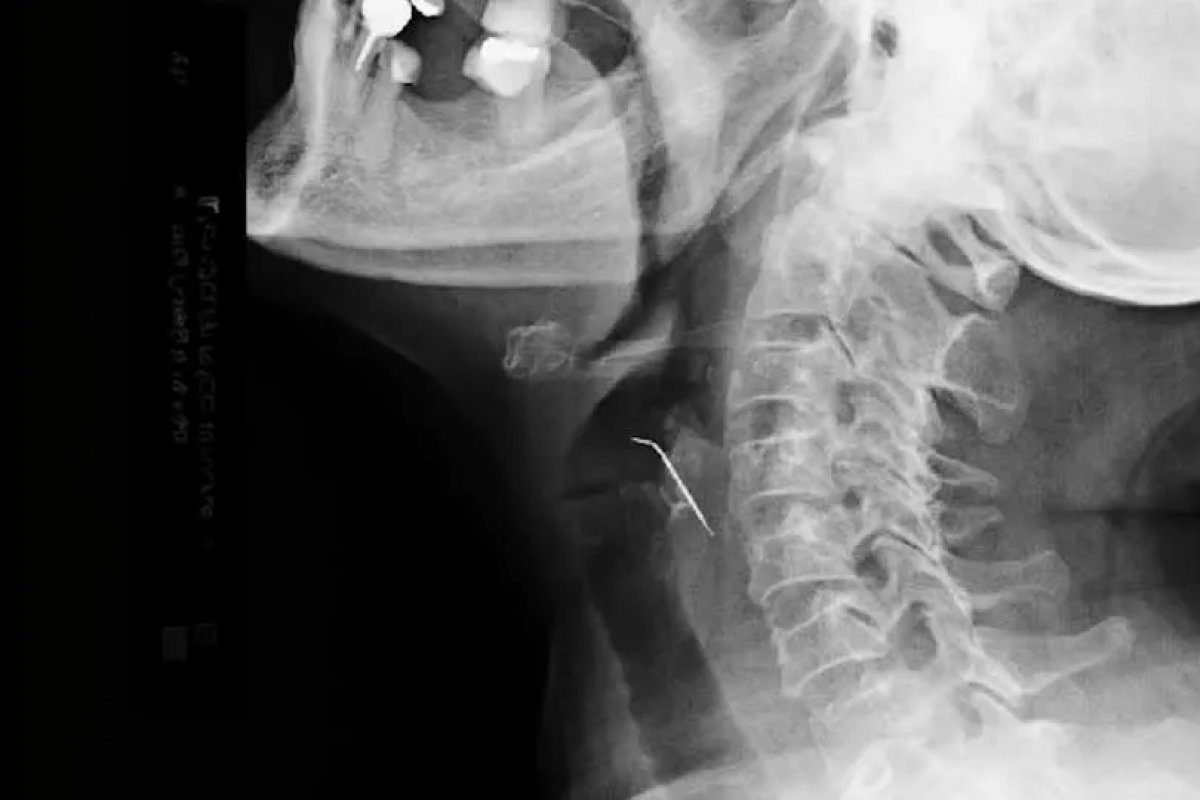

Uma mulher teve a vida salva por médicos após engolir, acidentalmente, um prego que estava misturado com carne de porco moída. O caso aconteceu no Peru e foi revelado por autoridades de saúde do país na última terça-feira (26).

De acordo com as informações divulgadas, a mulher, identificada como Célia Tello, de 68 anos, foi a até um hospital público após sentir desconfortos gastrointestinais. Após a realização de exames, ficou constatado que a mulher estava com um prego preso em sua artéria carótida.

Ela foi, então, encaminhada para uma cirurgia de emergência, onde os médicos removeram com sucesso o objeto e repararam a artéria afetada. Ela passa bem após a cirurgia e não corre risco de morte.